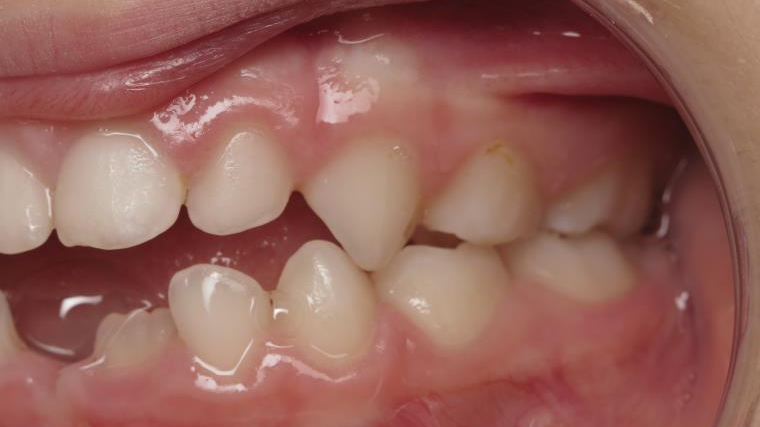

bilan début et en cours de traitement

inversion postérieur coté droit et espace entre l'arcade du haut et du bas (béance)